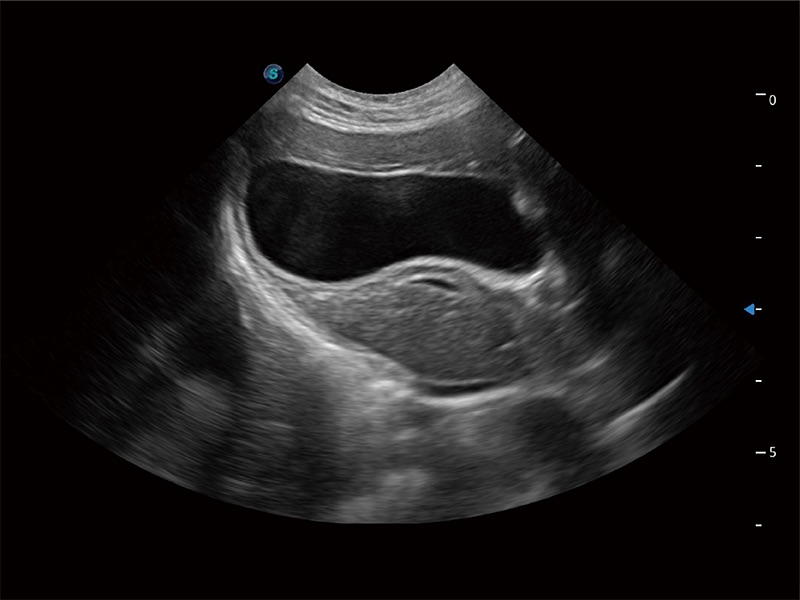

非线性融合造影成像充分利用谐波和基波信号,为难以观察的血流进行增强显像。可用于线阵、凸阵、微凸阵、相控阵探头。